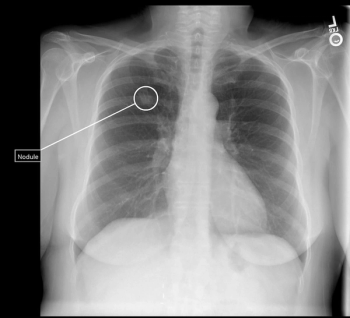

In addition to detecting missed lung nodules on X-rays, the AI-powered Qure.ai lung cancer continuum platform reportedly automates lung nodule measurement on CT scans and facilitates multimodality reporting.